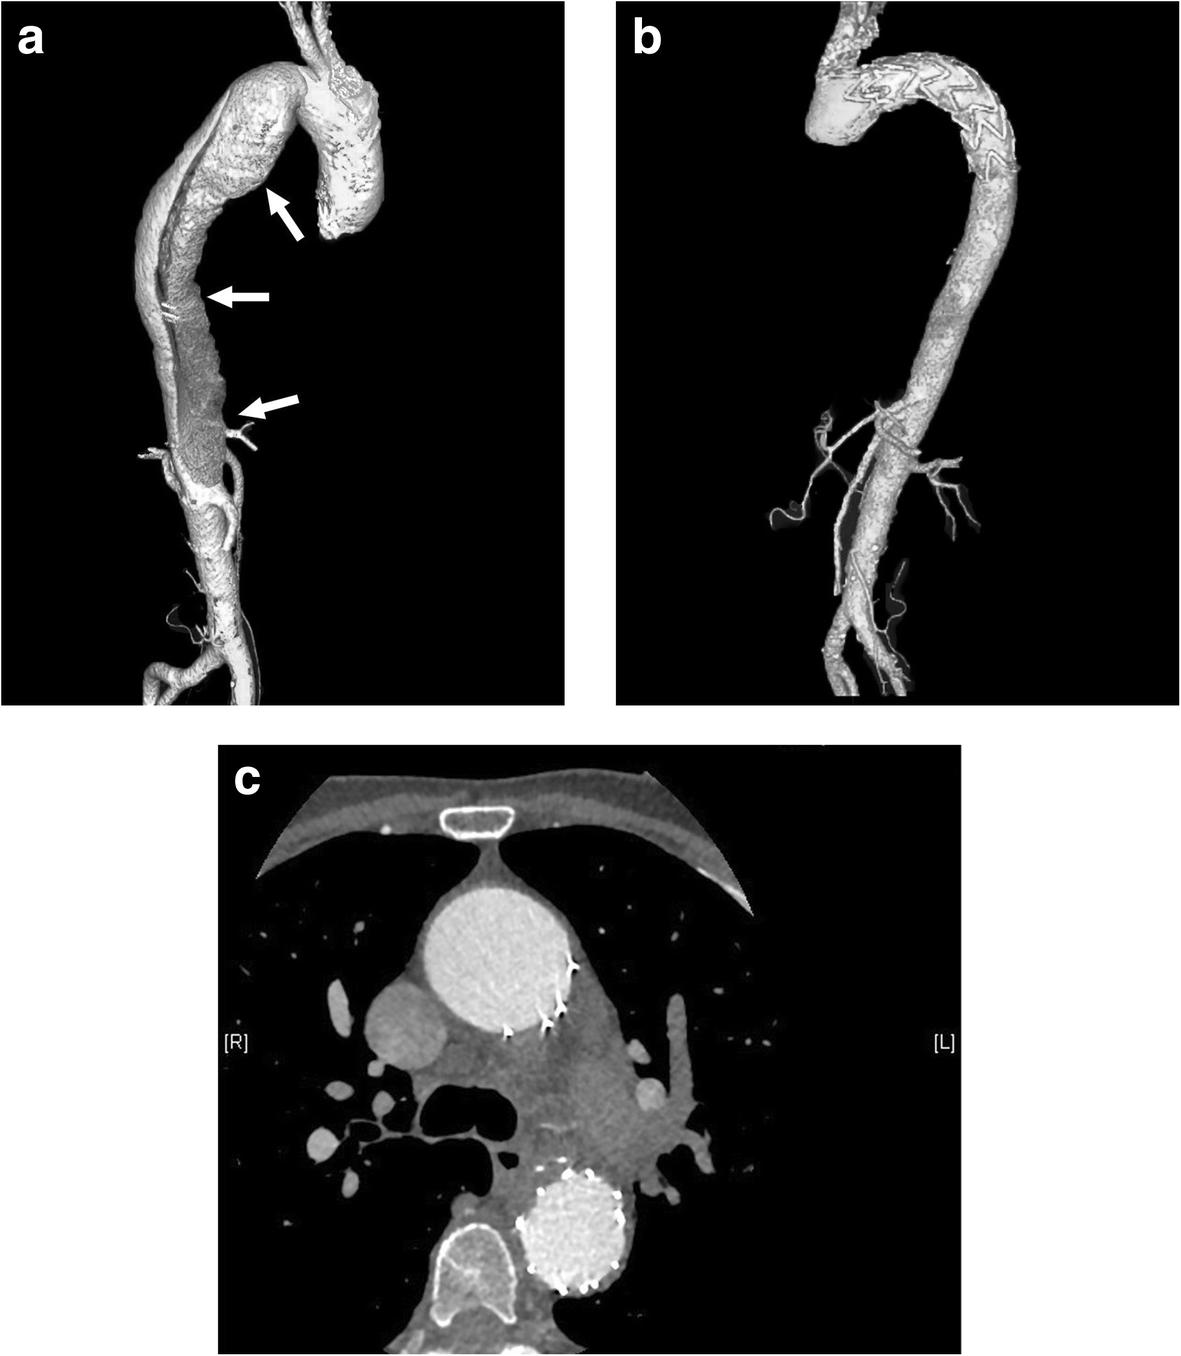

Fig. 1From: Is primary aldosteronism a potential risk factor for aortic dissection? A case report and literature reviewCT angiograms. a Dissection of the descending aorta in 2009 (arrows). b, c Repeat study in 2017 revealed no new dissection after TEVAR. CT: computed tomography; TEVAR: thoracic endovascular aortic repairBack to article page